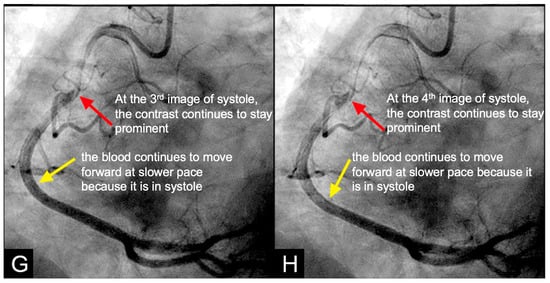

Cardiovascular Perspective. During a water hammer event within a coronary artery, the retrograde pressure wave would reflect and collide with the antegrade flow, first at the leading edge of the advancing flow, which is located at the transition from diastole to systole (red arrows in Figure 7E–H). The damage mechanism involves the superposition of forward and backward pressure waves, producing a pronounced pressure spike that may induce microtears in the endothelial layer [17]. These microtears may facilitate the migration of low-density lipoprotein (LDL) cholesterol molecules into the subintimal space, if the serum LDL level is high, starting the atherosclerotic cascade [18]. Additionally, the rapid flow reversal may disrupt normal shear stress distribution, further compromising the integrity of endothelial cells and weakening their role as structural barrier [18]. This pressure surge may be a key factor in intimal damage, triggering the cascade of events leading to atherosclerosis. The critical challenge lies in identifying and evidencing these damage mechanisms through currently available coronary angiographic images.

IN VIVO Coronary Flow Analysis. Angiographic Compression and Rarefaction Zones. Building on an advanced understanding of pressure wave reflections in pipes from an acoustic perspective, this investigation applied acoustic principles to analyze flow dynamics in coronary arteries. The primary objective was to delineate and quantify regions within the coronary arteries characterized by pockets of high-contrast density (compression) and moderate-contrast density (rarefaction), identified as antinodes (Figure 15A,B). Conversely, areas with minimal contrast were designated as nodes. These classifications were finalized at the end of the second cardiac cycle when the contrast was almost all washed out, leaving pockets of contrast which most likely were zones of compression or rarefaction (labeled as antinodes). The needs for identifying the five zones of compression and rarefaction (antinodes) and the minimal or lesion-free segments (nodes) within a coronary artery are listed in Table 4.

The secondary objective was to examine the relationship between antinodes and the presence of coronary stenoses, as well as between nodes and minimally diseased or lesion-free coronary segments. Ultimately, the investigation aimed to establish antinodes as potential markers for high-pressure surges linked to intimal damage. These locations of antinodes are used to construct a coronary acoustic activity (or action) map, enabling the identification of existing lesions, forecasting the progression of current lesions, and predicting the development of potential future lesions. Table 5 outlines the protocol on how to identify and label the five zones of compression and rarefaction (antinodes) and the minimal or lesion-free segments (nodes) within the coronary arteries. The protocol to identify the antinodes of compression and rarefaction and the nodes in between the antinodes uses the novel coronary dynamic angiographic technique. The protocol is listed in Table 5 and Figure 16A–E.

FIRST Compression Zone with High Contrast Concentration. Angiographic Identification. During diastole, coronary blood flow reaches a relatively high velocity. At the onset of systole, the contraction of the left ventricle abruptly interrupts this flow, triggering a water hammer effect. This results in the formation of a retrograde pressure wave, which collides with the antegrade flow at a critical timing when diastole transitions into systole. The initial reflection point, designated as location 1, is characterized by pockets of prolonged concentration of contrast agent, seen as a disorganized mixing of dark (contrast) and light (blood) materials (blue arrow in Figure 16E). These black-and-white pockets may signify turbulent flow, mirroring the surge of pressure in the local area (Figure 16A–D).

CRITICAL THINKING. High Concentration of Contrast at location 1 as a Marker of Compression Activity. During a typical cardiac cycle, antegrade blood flow accelerates during diastole and transitions rapidly into the systole, initiating a water hammer phenomenon that generates a retrograde pressure wave. This retrograde wave propagates at nearly the speed of sound and undergoes multiple reflections within one or two diastole–systole cycles along the length of a coronary artery. These reflections produce hundreds of retrograde pressure waves, which may synchronize with antegrade waves to form resonant patterns or, conversely, cancel out. The wave reflections occur at distinct locations: the diastole-to-systole junction (location 1), the coronary artery ostium (location 4), and the systole-to-diastole junction (location 2). The resulting wave dynamics display features of acoustic resonance, with regions of high contrast concentration corresponding to antinodes—pressure peaks associated with arterial damage or the progression of atherosclerosis (Figure 16E). High-contrast regions at locations 1 and 4, observed in coronary angiography, likely represent zones of compression and rarefaction, indicative of pressure surges that may compromise the intimal layer. The critical challenge lies in determining how these observations and hypotheses can be rigorously validated.

SECOND Rarefaction Zone with Moderate Contrast Concentration Angiographic Identification. Analogous to the retrograde propagation of a pressure wave caused by a water hammer toward the open end of a tube, when a high-density (compression) pressure wave reaches the ostial segment of a coronary artery—serving as an open interface—and contrast briefly displaces outward to equilibrate the pressure between the coronary artery and the aortic root. This displacement induces a localized pressure drop at the point of reflection. The resulting low-pressure zone, or rarefaction, propagates retrogradely through the coronary artery as a reflected rarefaction pulse (Figure 8 and Figure 17A–D). This phenomenon constitutes the second reflection point, labeled as 4 in Figure 16E, corresponding to the distal open end of the coronary artery, which is conceptualized as a tubular structure.

THIRD Rarefaction Zone with Moderate Contrast Concentration. Angiographic Identification. At the onset of the cardiac cycle, antegrade flow is initiated during diastole. During systole, the contraction of the left ventricle generates a pressure wave, characteristic of the water hammer effect, which propagates retrogradely and impacts the leading edge of the antegrade flow, causing intimal injury at this location (labeled 1) where diastole transitions to systole. This pressure wave continues its retrograde propagation, ultimately reaching the ostium of the artery, identified as location 4. Simultaneously, coronary flow advances forward during systole, albeit at a reduced velocity. Upon the end of systole, diastole resumes. The transition point where coronary flow shifts from systole to diastole is identified as location 2 where the elevated systolic pressure gives way to the lower diastolic pressure.

CRITICAL THINKINGS. Pressure Surge and Mechanism of Damage. When a pressure wave propagates through the blood of a coronary artery, it generates alternating regions of particle compression and rarefaction. At compression points (e.g., locations 1 and 3), there is a high concentration of contrast, whereas at rarefaction points (e.g., locations 2 and 4), the contrast concentration is less intense.

At location 1 with compression, corresponding to a pressure crest, the low-pressure antegrade flow during diastole is rapidly overtaken by a high-pressure surge during systole, producing a pronounced pressure peak. This abrupt surge induces disruption of the intima and increases the likelihood of severe damage leading to more severe lesions, plaque rupture, and the onset of acute coronary syndrome (ACS) (Figure 18A)

In contrast, at location 2 with rarefaction, representing a pressure trough, the transition de-escalating from high-pressure systolic flow to lower-pressure diastolic flow results in a pressure nadir. Unlike location 1, the absence of substantial pressure surges at location 3 generates minimal turbulence, causing less intimal damage. As a result, lesions in these regions are less severe, and the risk of triggering ACS is comparatively lower. Furthermore, the pressure surge within the very short artery remains limited due to the short distance, preventing the accumulation of sufficient pressure momentum (Figure 18A,B).

At nodal points, where pressure fluctuations and particle motion are minimal, the lack of significant dynamic stress inhibits lesion formation and progression. Consequently, these nodal segments exhibit minimal or no lesions (Figure 18C,D).

Coronary Acoustic Action MAP. The coronary flow investigations based on acoustics pinpointed pockets of high- or moderate-contrast concentrations, which might correspond to compression and rarefaction zones, respectively. Compression antinodes, linked to severe stenotic lesions, were believed to be due to rapid shifts from low-pressure diastolic flow to high-pressure systolic surges, causing turbulence and intimal disruption. Rarefaction antinodes, associated with milder lesions, were believed to be due to de-escalating transitions from high systolic pressure to lower diastolic pressure, resulting in less turbulence and milder injury. Nodes remained unaffected because there was no disorganized flow in its segments. An acoustic action map based on antinode and node locations could facilitate identifying current lesions and predicting future ones (Figure 19).